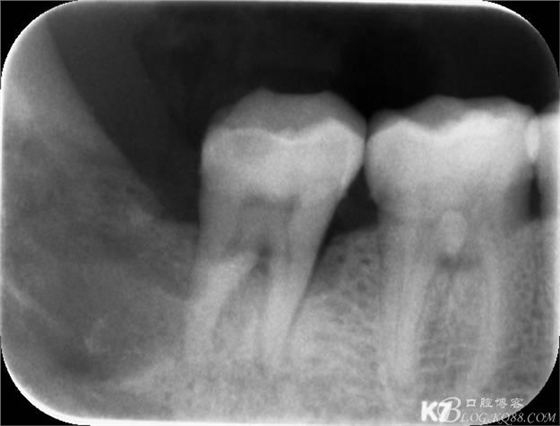

48未萌出,47遠中可探及深約7mm的牙周袋。頰側47、48之間牙齦紅腫,有少量血性滲出。X線根尖片顯示:48牙冠反轉倒置,47遠中牙槽骨吸收明顯。CBCT顯示:48牙冠近中面位于下頜管內。

10.術后根尖片: